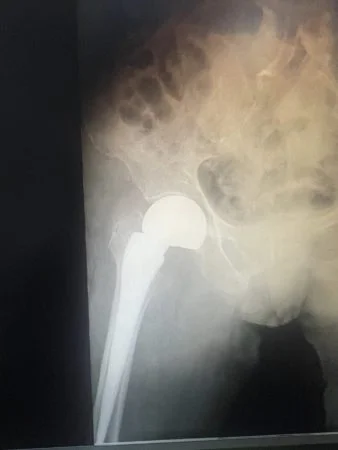

Bệnh nhân là cụ bà H.T.N 102 tuổi nhập viện cấp cứu ngày 6/11/2022 trong tình trạng đau và mất vận động vùng đùi trái. Tại bệnh viện, sau khi tiến hành các xét nghiệm, X- quang, bác sĩ xác định cụ bà bị gãy cổ xương đùi trên và đủ điều kiện để phẫu thuật thay khớp háng trái bán phần.

Bệnh viện Thống Nhất với thế mạnh về Lão khoa cùng với sự phối hợp của nhiều chuyên khoa như khoa PT-GMHS, nội Tim mạch… ngày 9/11/2022 ca phẫu thuật thành công sau 45 phút tiến hành, bệnh nhân được thay khớp háng bán phần, không xảy ra biến chứng sau phẫu thuật.